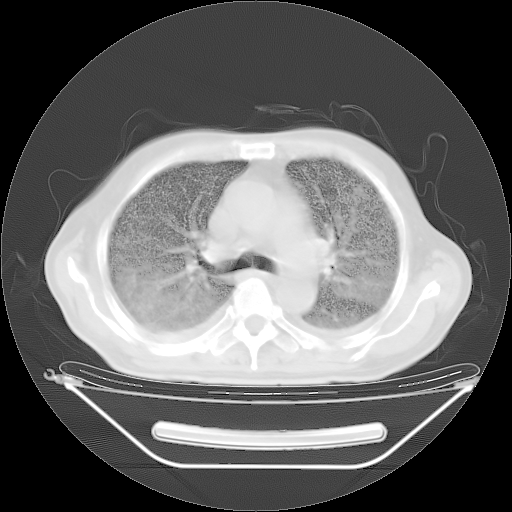

今天复查肺部CT,发现双肺广泛磨玻璃样改变。所以我把3月19日和5月9日相隔50天的肺部CT上传。请大家会诊。

5月9日肺部CT(在4月27日齐鲁医院肺部CT描述部分肺组织磨玻璃样改变,12天后肺组织广泛磨玻璃样改变)

大致读了系列胸部CT:纵隔窗无明显异常,肺窗:从4、27至今:主要是双肺中下野外带可见毛玻璃样改变,目前处于急性肺泡炎阶段,至于原因考虑1、结替组织或胶原血管性疾病所致?2、恶性疾病如恶组在肺部所致的表现或细支气管肺泡癌?3、药物或其它原因如肺蛋白沉着症所致肺泡炎目前不太可能?总之,明天就去请我院的呼吸科、感染科、血液科和临免专家会诊哈。